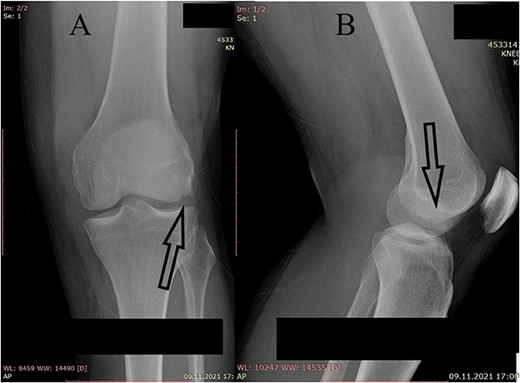

A plain X-ray of the left knee revealed a single defect of the lateral femoral condyle in the anteroposterior (AP) view. The lateral view showed a free bone fragment with a defect (Fig. 1A and B). Additional diagnostic imaging was performed. A computerized tomography (CT) scan revealed multifragmentary (three fragments) fracture of the lateral femoral condyle accompanied by a fracture of the left patella (Fig. 2). The fracture was classified as 33B3.2 according to the Association for Osteosynthesis–Orthopaedic Trauma Association (AO/OTA), Type II C (according to Letenneur) [2]. It was decided that single-approach surgery (posterior or anterior) would be insufficient for acceptable anatomic reduction and proper fixation of all the fragments because of the fracture complexity. The preoperative plan consisted of a posterior-first approach (extended posterior approach to the proximal tibia) for fixation of the largest (posterior) fragment (Fig. 3) followed by an arthroscopic anterior approach (for anterior fragment fixation). The predetermined time interval between the two procedures was to allow the healing of the joint capsule after the index surgery. Operative fixation of the patellar fracture was not indicated.

CT scan of the left knee (sagittal) with three fragments (arrows) and patellar fracture (arrowhead).